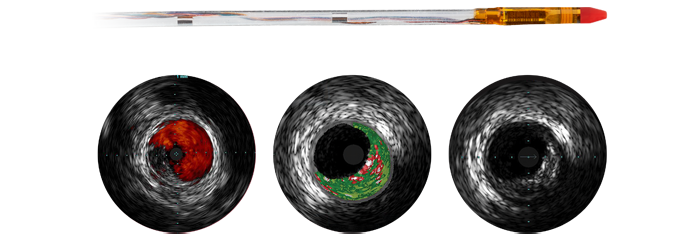

À medida que mais pacientes de doença arterial coronariana são considerados para terapia intervencionista minimamente invasiva, o planejamento ideal do tratamento é dificultado pelo fato de que a angiografia coronária em 2D tem limitações para detectar e avaliar a estenose coronária. Os dados não estão consistentemente e significativamente conectados pré e intra-procedimento, o que adiciona tempo e complexidade ao planejamento do tratamento. Projetamos nossas soluções de cardiologia para superar esses desafios a fim de que você possa perceber os benefícios da eficiência clínica no laboratório de cateterismo:

A terapia guiada por imagem, iFR, IVUS e o monitoramento hemodinâmico, bem como o planejamento antes do procedimento cardíaco e aplicações avançadas, estão todos conectados à interface de terapia guiada por imagem para permitir a visualização, manipulação e configuração personalizada no monitor usando um único controlador na mesa ou na sala de controle.